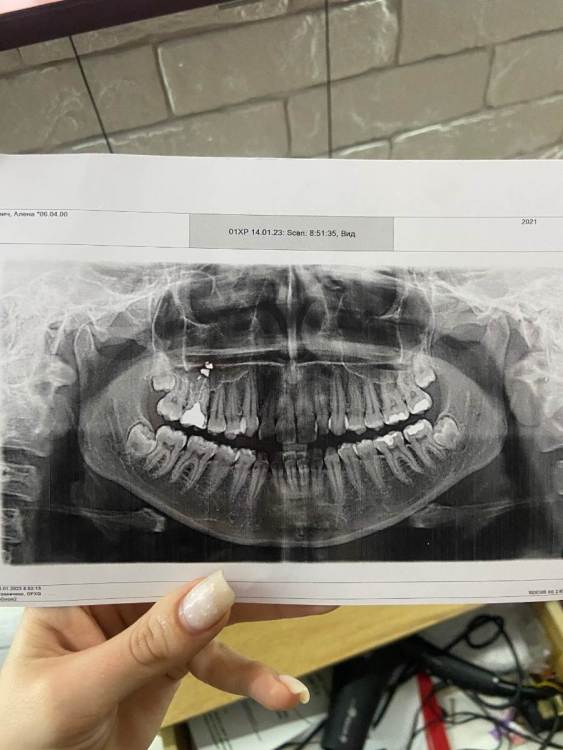

alenasuslova2000 Опубликовано 20 января, 2023 Поделиться Опубликовано 20 января, 2023 Подскажите, что теперь делать с 6 зубом? Полтора года назад пломбировала, и видимо материал теперь в корне, врач поставил брекиты, сказал что такое бывает и так ходят с этим материалом если он не беспокоит, на тот момент он у меня не болел и я про него ничего не говорила , но вообще он в течении года то болел то переставал, а я не придала этому значения( что делать? Ссылка на комментарий

red_butler Опубликовано 22 января, 2023 Поделиться Опубликовано 22 января, 2023 20.01.2023 в 13:22, alenasuslova2000 сказал: что делать? Кт с придаточными пазухами носа Ссылка на комментарий